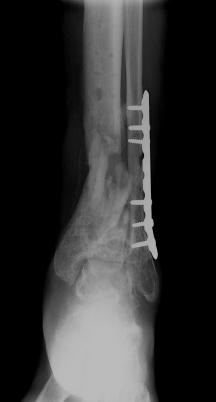

Post-corrective surgery X-Rays of the damaged right & left legs / ankles

The first two x-rays show Liam’s left ankle and pelvis prior to the accident. For comparison purposes it is interesting to see the

differences. The next x-rays were taken after the corrective surgery performed by Dr. Armendariz. Noticed that Dr. Armendariz has used tibia

bracing and also aligned the bone fragments of the left leg so that they could heal in the proper orientation. The external fixation has been

removed and Liam’s left foot has been returned to a more natural alignment.